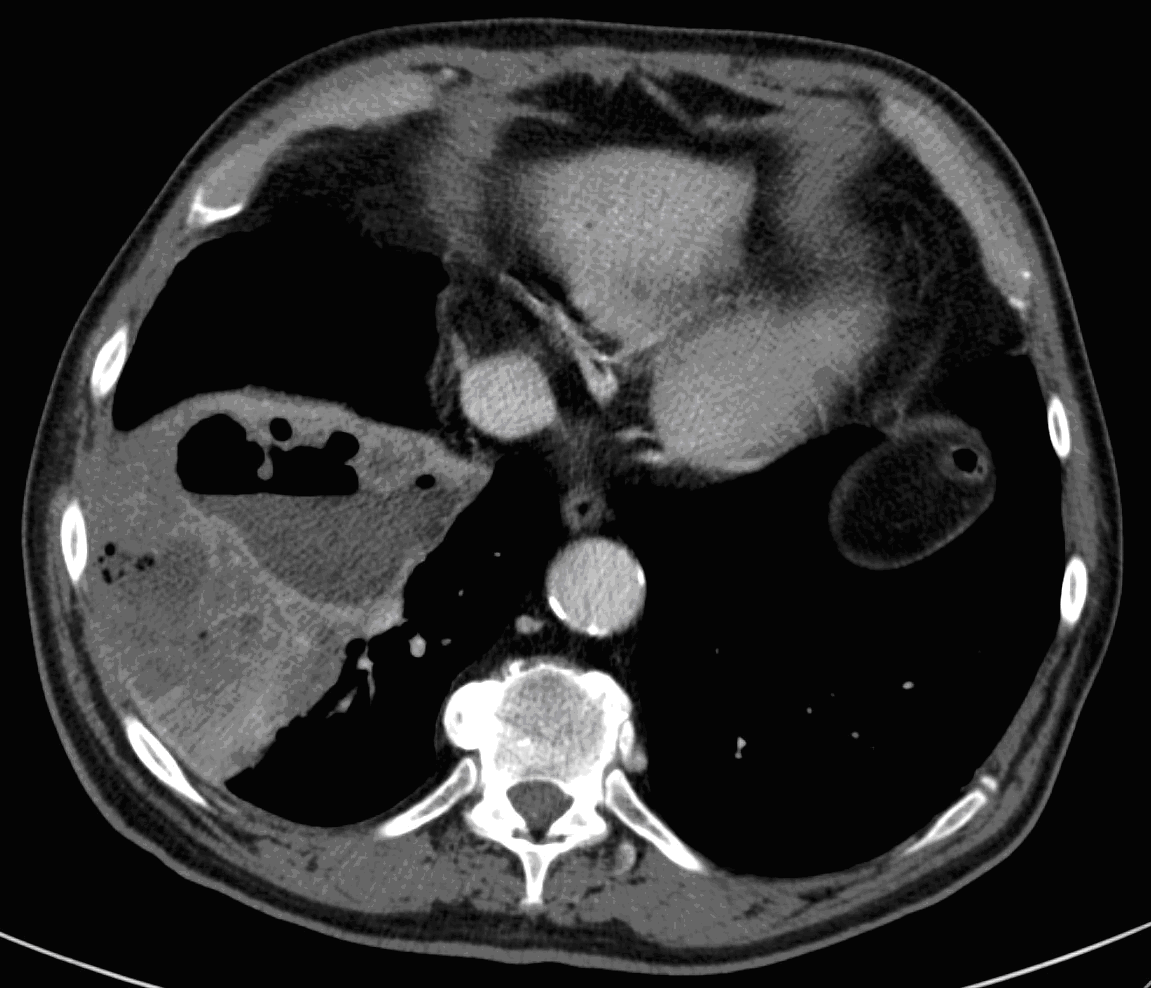

26. ARDS, CT, coronary reconstruction

52 year old woman, dyspnea, septic shock.

Bilateral opacity according to rough, diffuse interstitial edema, irregular atelectasis and bronchogram in the basal segments